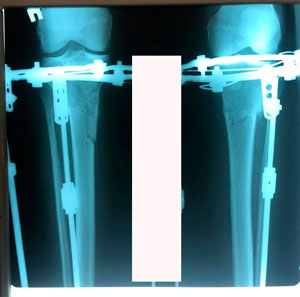

Диагноз: варусная деформация голеней + Ротация с обеих сторон.

Дата операции - 09.07.2020

рентген перед фиксацией